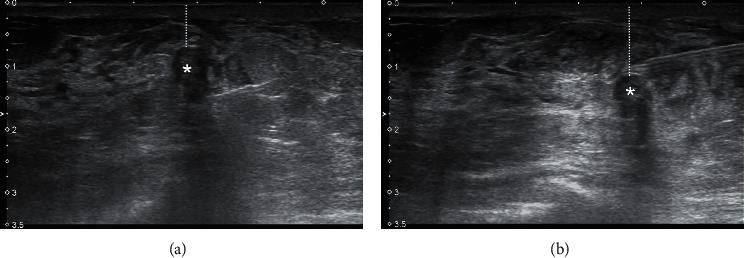

The purpose of this study was to investigate the feasibility of the percutaneous radiofrequency (RF) excision system (BLES) as a primary method of diagnosis and removal of small breast masses.

Ninety-six lesions in 95 patients with 50.5 ± 8.4 years of age were treated in a five-year period by a single operator. Inclusion criteria were as follows: size (<20 mm), depth (>10 mm), and indeterminate or suspicious radiological features (74 BI-RADS 3 and 22 BI-RADS 4). The procedure was performed under ultrasound (US) guidance using 6 G retriever probes with 12-, 15-, and 20-mm baskets.

方法

在五年期间,由一名外科医生对 95 名患者的 96 个病灶进行了治疗,这些患者的年龄为 50.5±8.4 岁。纳入标准为:大小(<20mm)、深度(>10mm)以及不确定或可疑的影像学特征(74 个 BI-RADS 3 和 22 个 BI-RADS 4)。该过程在超声(US)引导下进行,使用 6G 取物探针和 12、15 和 20mm 的篮子。